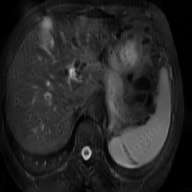

This work presents a novel framework CISFA (Contrastive Image synthesis and Self-supervised Feature Adaptation)that builds on image domain translation and unsupervised feature adaptation for cross-modality biomedical image segmentation. Different from existing works, we use a one-sided generative model and add a weighted patch-wise contrastive loss between sampled patches of the input image and the corresponding synthetic image, which serves as shape constraints. Moreover, we notice that the generated images and input images share similar structural information but are in different modalities. As such, we enforce contrastive losses on the generated images and the input images to train the encoder of a segmentation model to minimize the discrepancy between paired images in the learned embedding space. Compared with existing works that rely on adversarial learning for feature adaptation, such a method enables the encoder to learn domain-independent features in a more explicit way. We extensively evaluate our methods on segmentation tasks containing CT and MRI images for abdominal cavities and whole hearts. Experimental results show that the proposed framework not only outputs synthetic images with less distortion of organ shapes, but also outperforms state-of-the-art domain adaptation methods by a large margin.